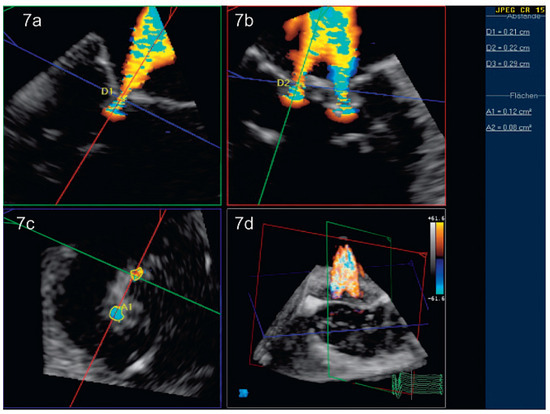

Dreidimensionale Echokardiographie zur Beurteilung der Mitralklappe

by Patric Biaggi, Christian Felix, Matthias Greutmann, David Hürlimann, Dominique Bettex and Felix C. Tanner

Using two-dimensional echocardiography, the complex anatomy of the mitral valve needs mental reconstruction into its three-dimensional shape. The power of both transthoracic and transesophageal three-dimensional echocardiography (3DE) lies in its possibility of showing the complex mitral valve anatomy in one single image, as [...] Read more.

Using two-dimensional echocardiography, the complex anatomy of the mitral valve needs mental reconstruction into its three-dimensional shape. The power of both transthoracic and transesophageal three-dimensional echocardiography (3DE) lies in its possibility of showing the complex mitral valve anatomy in one single image, as opposed to the mental reconstruction based on multiple two-dimensional images and schematic assumptions. Several 3DE modalities are used in daily life, including real time (“live”) modes as wells as postprocessed images. 3DE is of special interest in the evaluation of mitral stenosis, complex mitral valve prolapse and mitral valve prostheses. It has an established role in the perioperative mitral valve assessment during mitral valve surgery as well as during percutaneous mitral valve procedures. Limitations of 3DE are relatively low frame rates, an important learning curve as well as timeconsuming processing. Full article